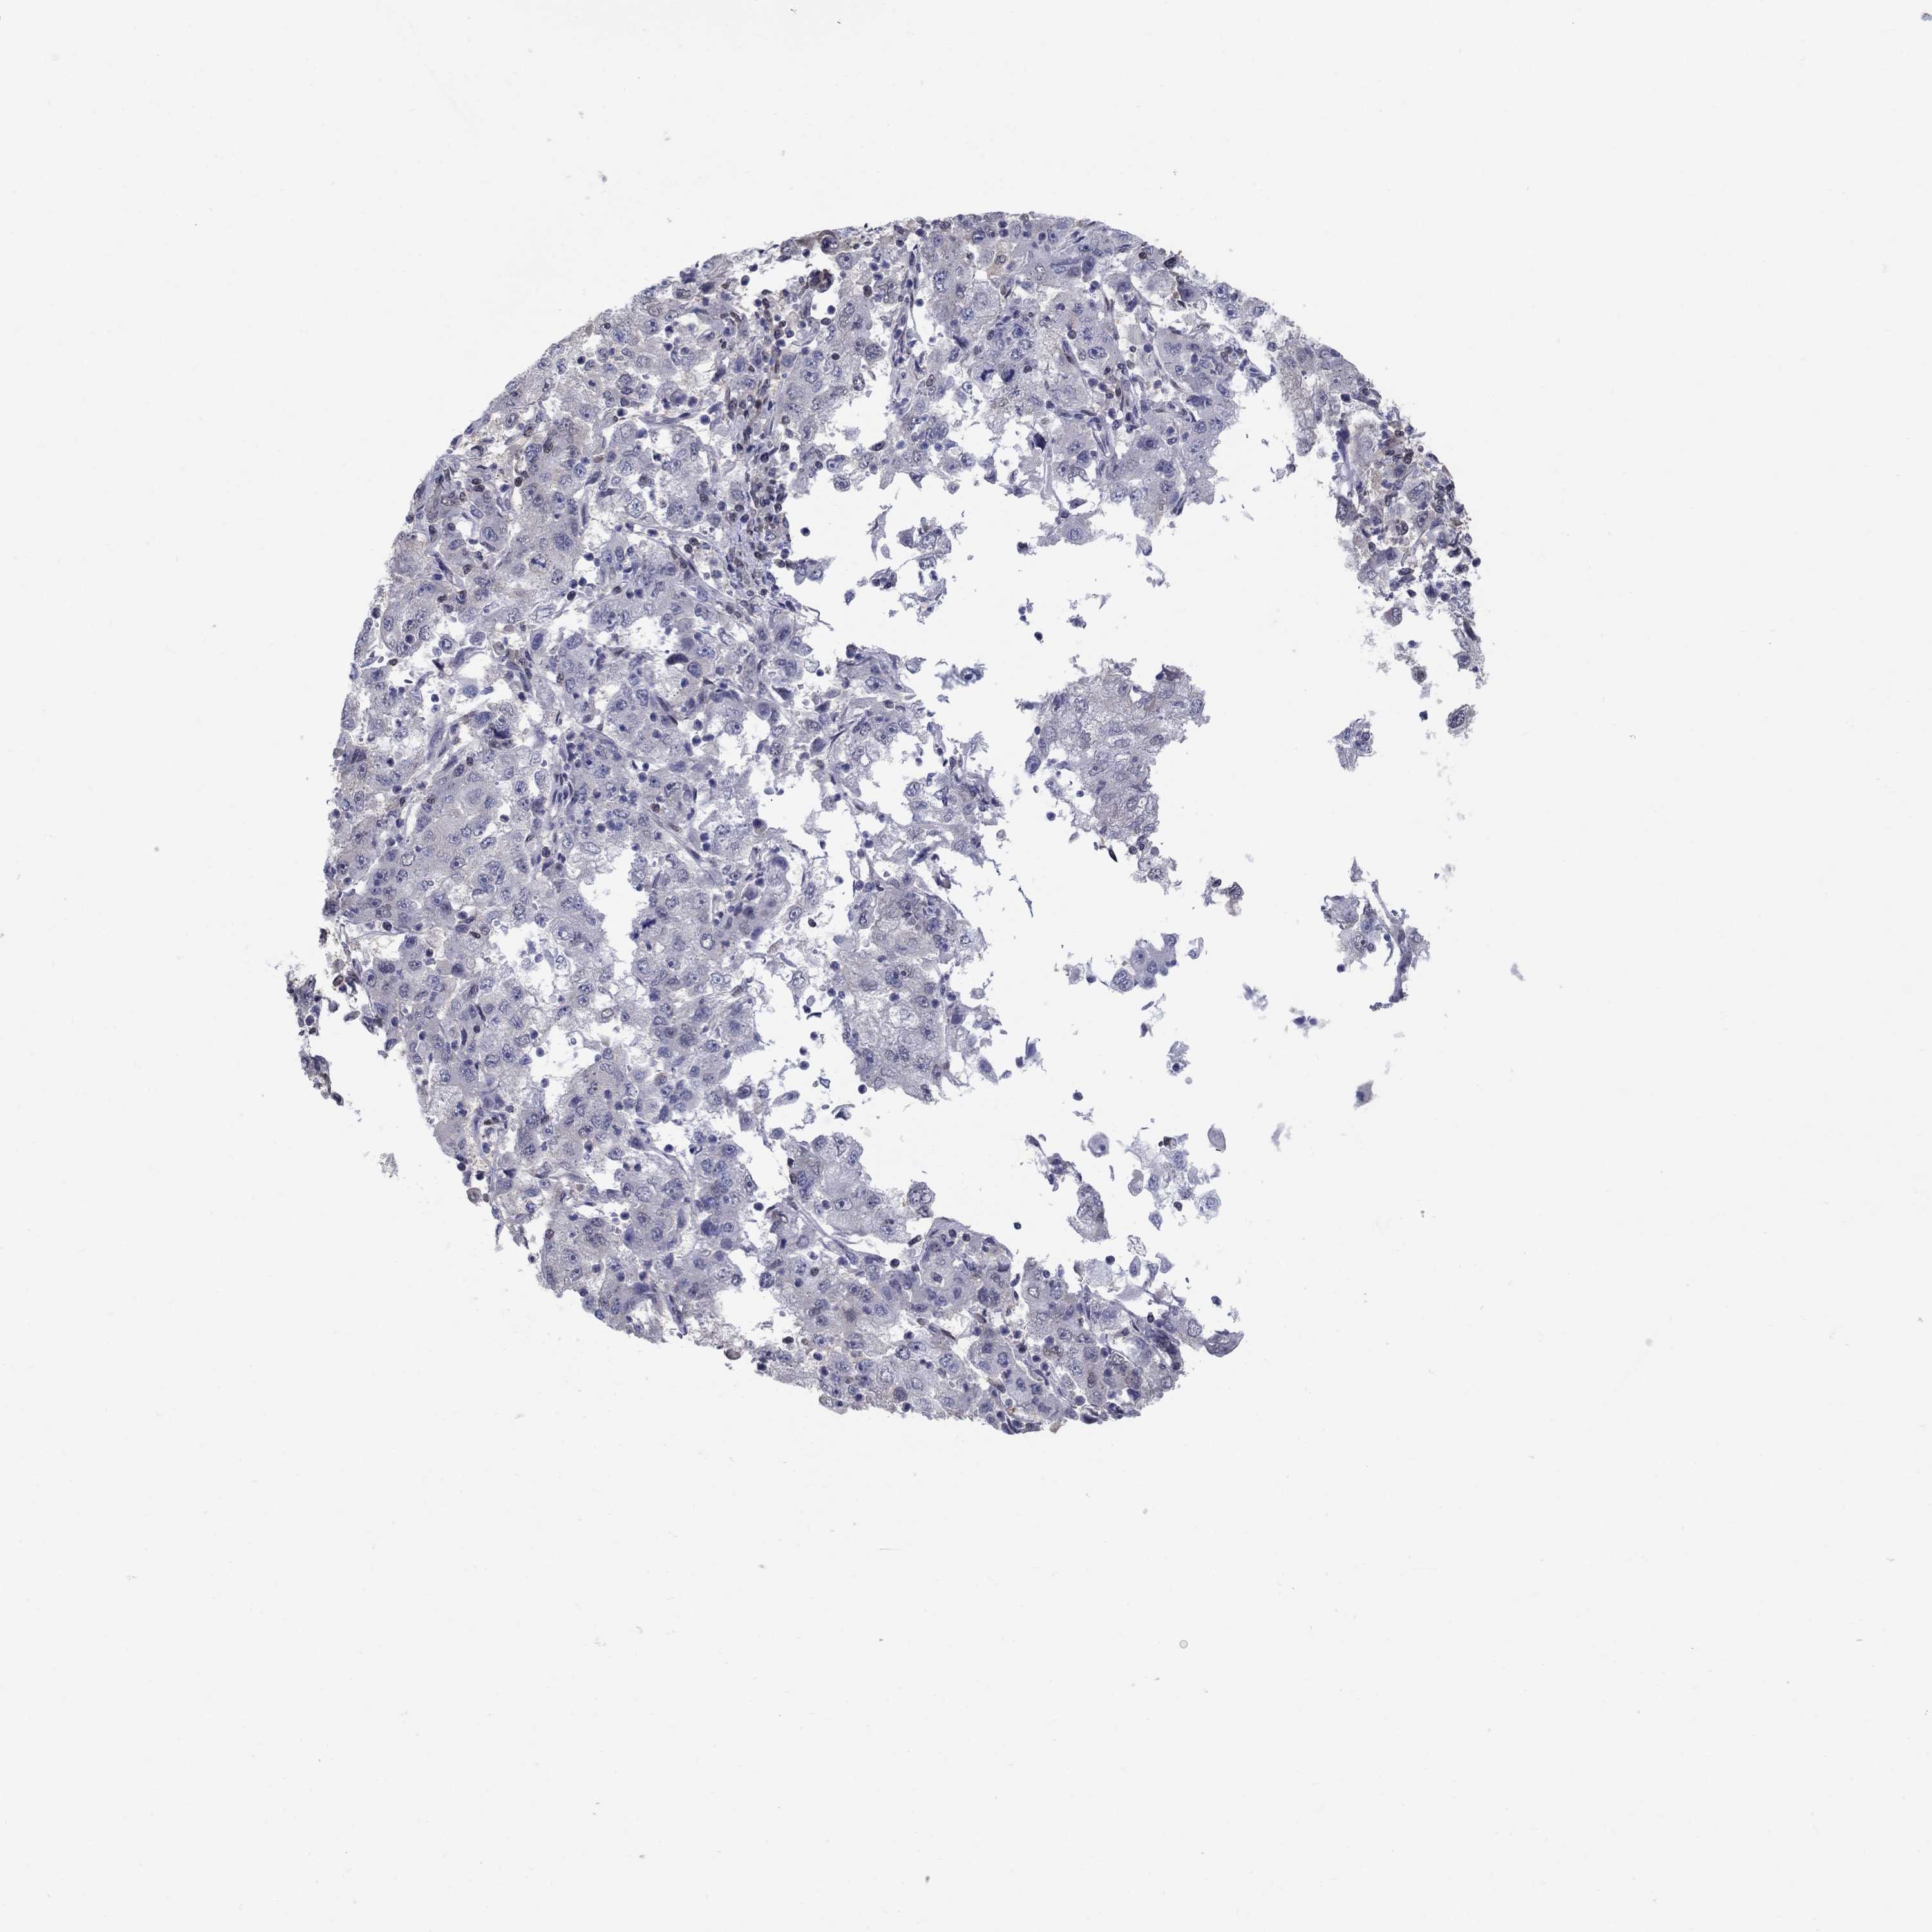

CERVICAL CANCER - Protein expressioni

A mouse-over function shows sample information and annotation data. Click on an image to view it in a full screen mode. Samples can be filtered based on level of antibody staining by selecting one or several of the following categories: high, medium, low and not detected. The assay and annotation is described here.

Note that samples used for immunohistochemistry by the Human Protein Atlas do not correspond to samples in the TCGA dataset.

Antibody stainingi

Antibody staining in the annotated cell types in the current human tissue is reported as not detected, low, medium, or high, based on conventional immunohistochemistry profiling in selected tissues. This score is based on the combination of the staining intensity and fraction of stained cells.

Each image is clickable and will lead to virtual microscopy that enables deeper exploration of all samples and also displays staining intensity scores, fraction scores and subcellular localization as well as patient and tissue information for each sample.

Antibody HPA042294

Staining

High

Medium

Low

Not detected

Intensity

Strong

Moderate

Weak

Negative

Quantity

>75%

75%-25%

<25%

None

Location

Nuclear

Cytoplasmic/membranous

Cytoplasmic/membranous,nuclear

Squamous cell carcinoma, NOS

Adenocarcinoma, NOS